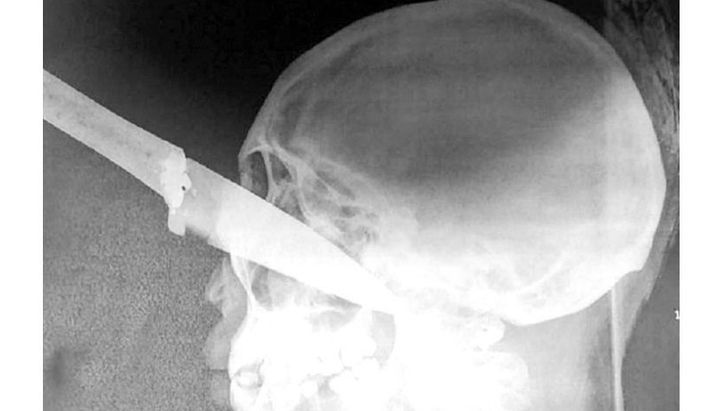

Por causas que se tratan de establecer, Florencia Micaela Ruiz, de 22 años, fue increpada por cuatro jovencitas. Una de ellas empuñaba un cuchillo y con mucha furia le aplicó un puntazo en el ojo izquierdo. Fue con fuerza y llegó a una gran profundidad, ya que el arma blanca quedó clavada en el rostro de la chica.

Frente al consultorio se vivieron momentos de horror porque muchos observaron a la víctima con el cuchillo clavado en el ojo y completamente ensangrentada.

A Florencia Micaela Ruiz lograron extirparle el cuchillo y fue intervenida quirúrgicamente en el hospital San Bernardo de Salta capital y permanece en delicado estado, en terapia intensiva, con pronóstico reservado.

La chica entró al quirófano, de urgencia, alrededor de las 21 del jueves. La cirugía estuvo a cargo, en primera instancia, de cirujanos vasculares y en un segundo momento de oftalmólogos que practicaron una evisceración ocular, porque tuvieron que eliminar el contenido del ojo en el que recibió la profunda cuchillada.